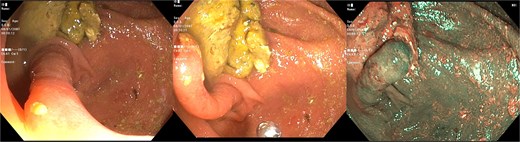

Subsequently, in January 2025, a contrast-enhanced computed tomography (CT) scan was performed for further evaluation of the lesion. The formal outpatient CT report described only sigmoid diverticulosis. The patient was then scheduled for an in-hospital polypectomy. During the repeat colonoscopy performed in May 2025, the same cecal lesion was confirmed, becoming evident after removal of the overlying fecal content. The lesion, originating from the appendiceal orifice, was evaluated by two endoscopists and a surgical consultant. Its structure and mucosal appearance were not suspicious for a polyp but rather consistent with an inverted appendix (Fig. 1).

Colonoscopic image of the cecum showing characteristic features consistent with an inverted appendix.